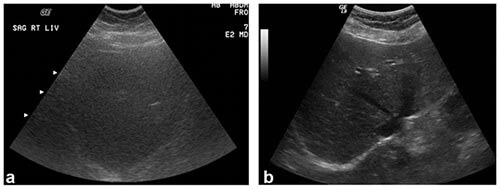

Body habitus impacts ultrasound imaging quality, predominantly as related to the amount and distribution of adipose tissue. Adipose tissue attenuates sound waves, decreasing penetration of the ultrasound beam. Image quality is often worse in patients with a greater amount of subcutaneous, rather than intraperitoneal, adipose tissue. Subcutaneous adipose tissue immediately attenuates the ultrasound beams, hindering their ability to penetrate internal organs. This can have significant clinical impacts. For example, multiple ultrasound exams may be necessary to accurately characterize fetal anatomy in patients with high body mass index

(BMI)3-5.

Liver ultrasound images showing increased attenuation of ultrasound beams in a patient weighing 350 lbs (left) compared to a patient weighing 150 lbs (right). Note, the decreased image detail in image (a) as compared to image

(b).1